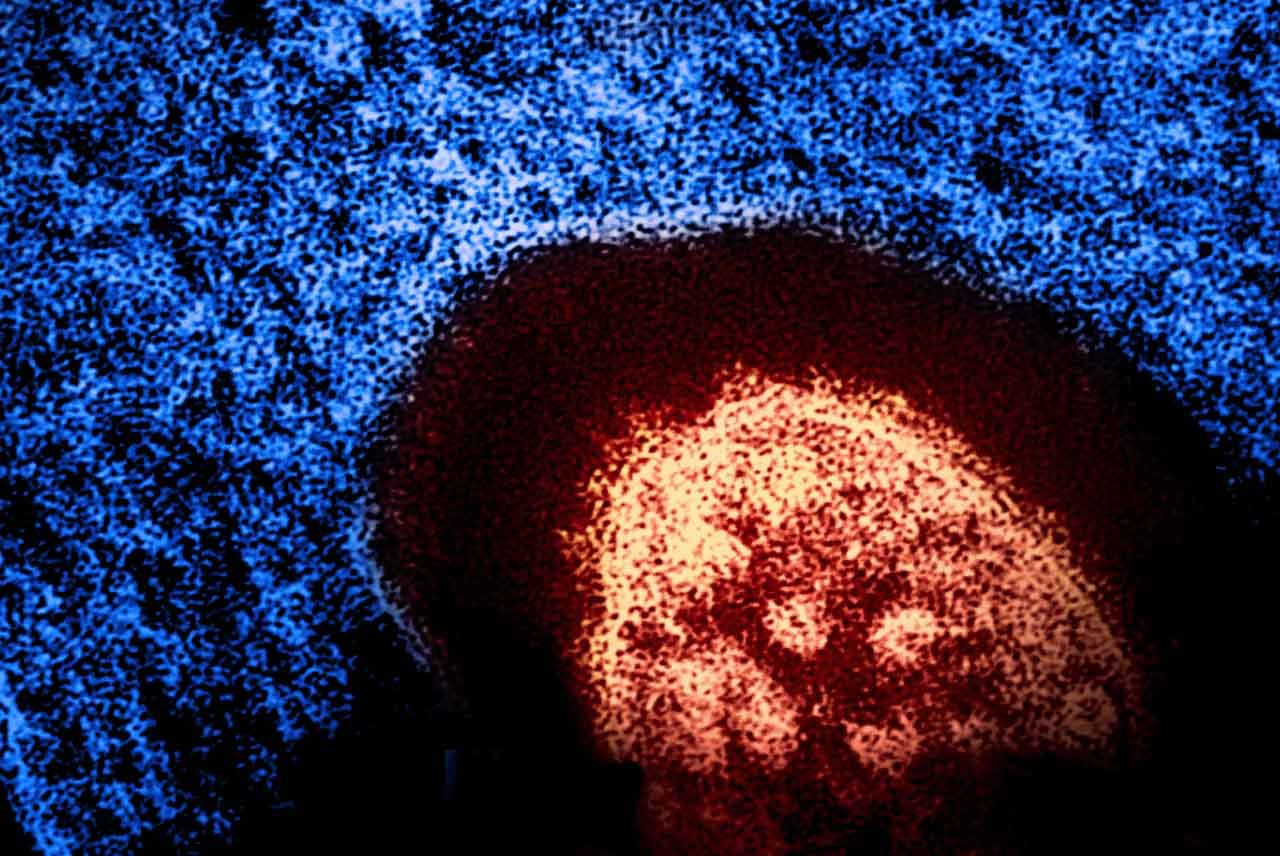

Yesterday, the Oregon Health Authority OHA alerted health care providers that measles was detected in Marion County wastewater in a sewage sample through routine testing on October 6, implying that at least one person in the county has measles.

The precautionary health care alert, sent via the Health Alert Network (HAN), was issued after the positive sample collected on October 6 from a wastewater (sewerage) treatment plant in Marion County showed that at least one person is infected with the measles virus within the local area serviced by the wastewater treatment plant.